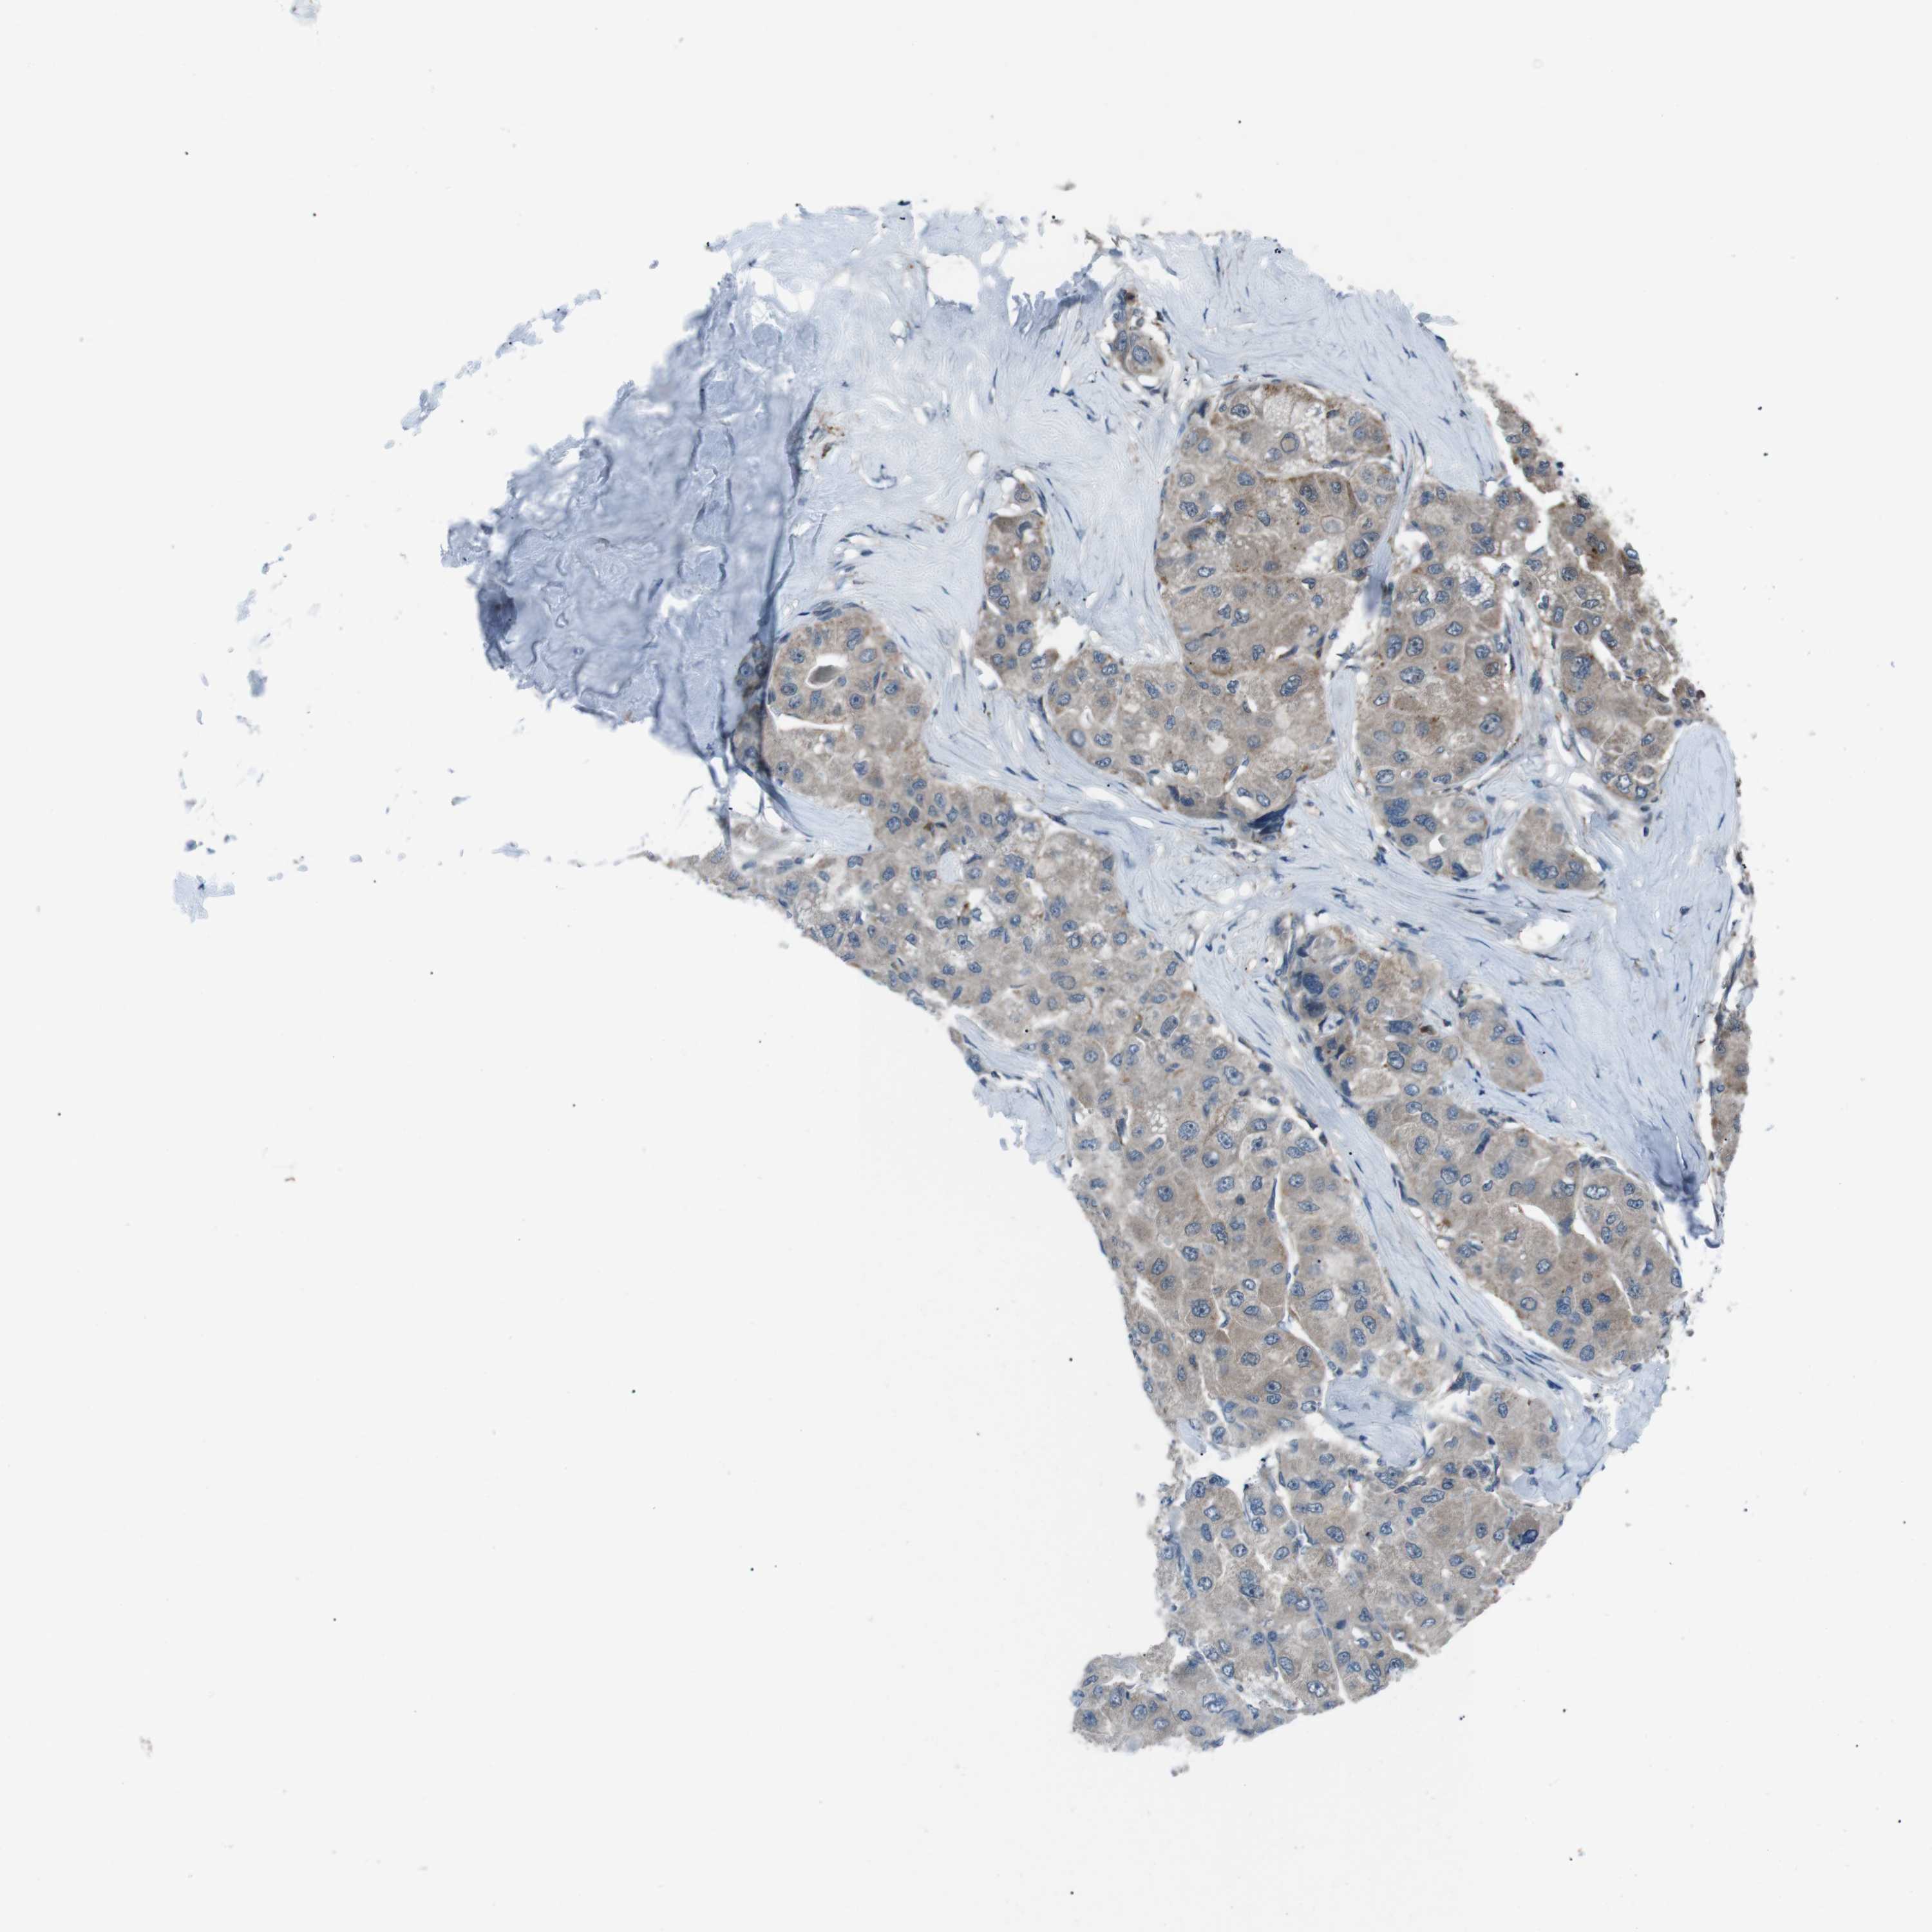

LIVER CANCER - Protein expressioni

A mouse-over function shows sample information and annotation data. Click on an image to view it in a full screen mode. Samples can be filtered based on level of antibody staining by selecting one or several of the following categories: high, medium, low and not detected. The assay and annotation is described here.

Antibody stainingi

Antibody staining in the annotated cell types in the current human tissue is reported as not detected, low, medium, or high, based on conventional immunohistochemistry profiling in selected tissues. This score is based on the combination of the staining intensity and fraction of stained cells.

Each image is clickable and will lead to virtual microscopy that enables deeper exploration of all samples and also displays staining intensity scores, fraction scores and subcellular localization as well as patient and tissue information for each sample.

Antibody HPA007293

Antibody CAB009771

Staining

High

Medium

Low

Not detected

Intensity

Strong

Moderate

Weak

Negative

Quantity

>75%

75%-25%

<25%

None

Location

Nuclear

Cytoplasmic/membranous

Cytoplasmic/membranous,nuclear

Cholangiocarcinoma

Carcinoma, Hepatocellular, NOS